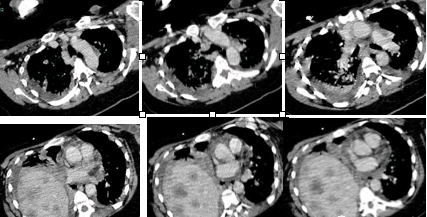

患者肝脏体积增大,里面密密麻麻分布着大小不一的结节,右侧膈肌明显抬高,使得右肺体积明显缩小;右肺门与肺动脉交界处有一个肿块(如下图):

原本以为腹中的胎儿落地,患者的膈肌应该能下移,然后能够轻松地躺下来了。可是转到普通病房后,患者仍然每日只能端坐着,躺下来不到半分钟就喘不过气来。查体发现患者有很明显的腹部矛盾运动,平卧位吸气的时候腹部是陷进去的。难道患者的膈神经受到侵犯了?